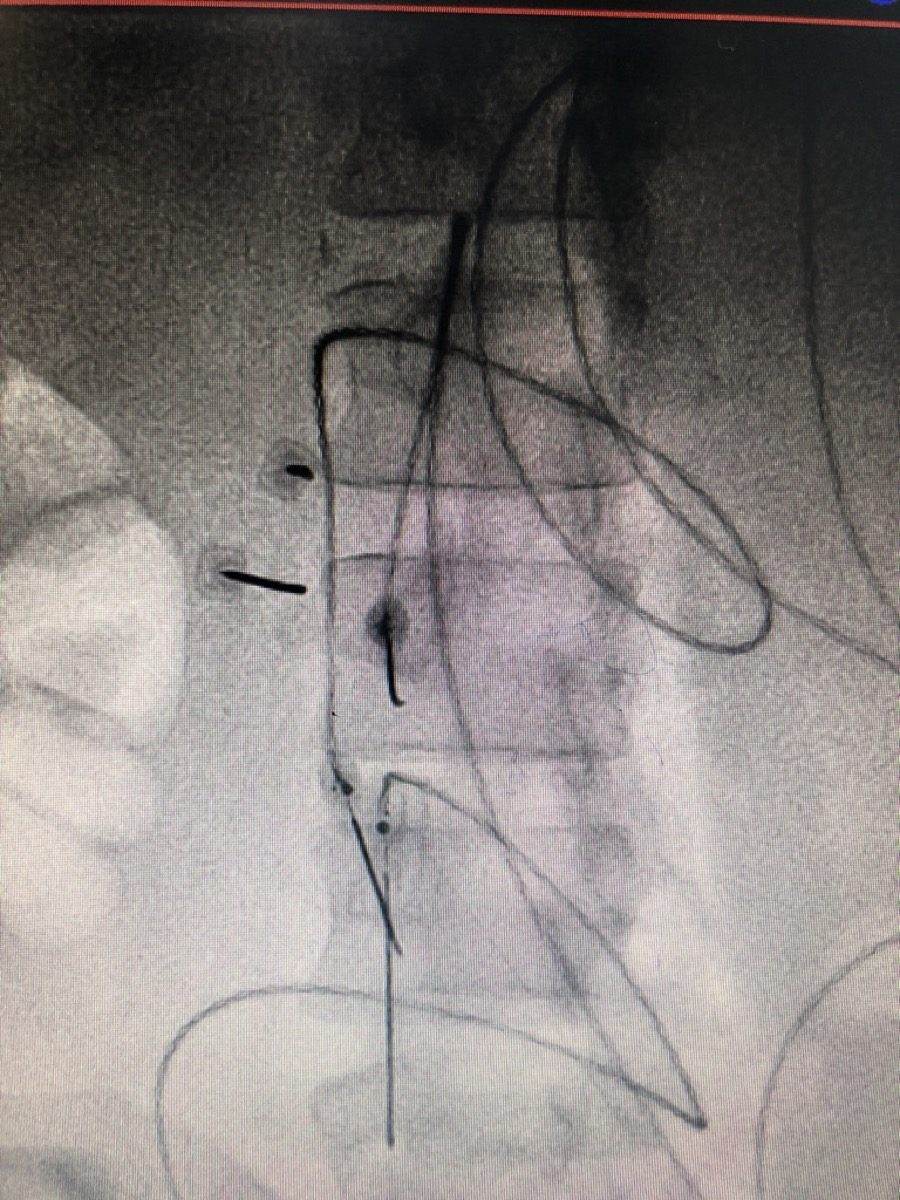

4. Diagnostic nerve block to test whether peripheral nerve activity is driving the pain

• Stump Neuroma Injection and RFA to diagnose and treat painful neuromas in the residual limb, reducing the abnormal peripheral signal that feeds into phantom pain

Yes. Many neuromas respond very well to image-guided injections with local anaesthetic and steroid. When pain returns after initial injection relief, radiofrequency ablation of the neuroma provides longer-lasting results by disrupting the nerve tissue generating the abnormal signals. Surgical excision is reserved for cases that do not respond to these minimally invasive options. Dr. Ashu Kumar Jain will assess whether the neuroma is the primary pain generator with a diagnostic block before recommending any definitive treatment.